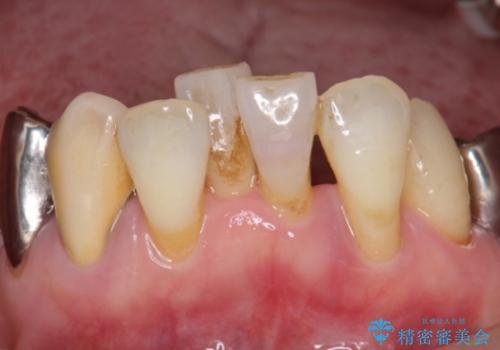

- 下の前歯(左下2)と奥歯の動揺がひどくなってきたことを主訴に来院された患者様です。

精査したところ、前歯の咬み合わせが反対になっていること、下の奥歯(下顎両側67)が4本欠損していることから動揺が生じていました。

入れ歯も抵抗があるとのことから、相談を重ね、今の状態では保存不可能な下の前歯(左下2)を抜去し、ブリッジや連結補綴により動揺を抑えることにしました。

また、咬み合わせが反対になっている上の前歯(左上2)も補綴で形を変えることにより、咬合を改善しました。